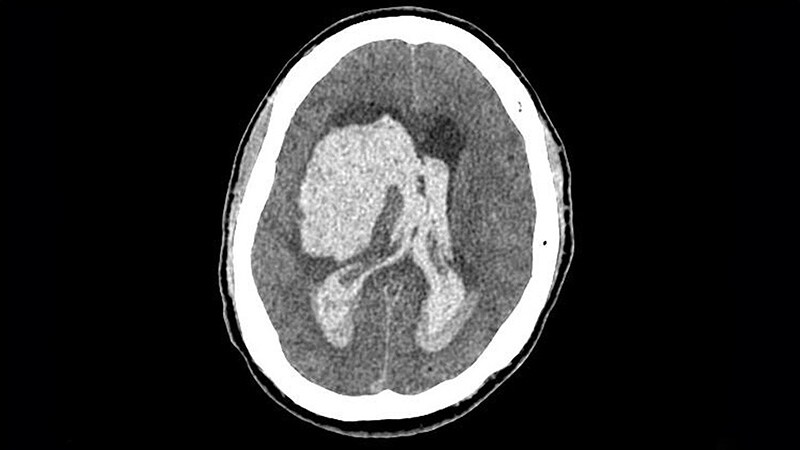

Combo Thrombolytic Approach Fails to Reduce ICH in StrokeThe DUMAS study showed no benefit on the primary outcome of all ICH with low-dose alteplase followed by mutant pro-urokinase;

but there were promising signs of a potential reduced bleeding risk.